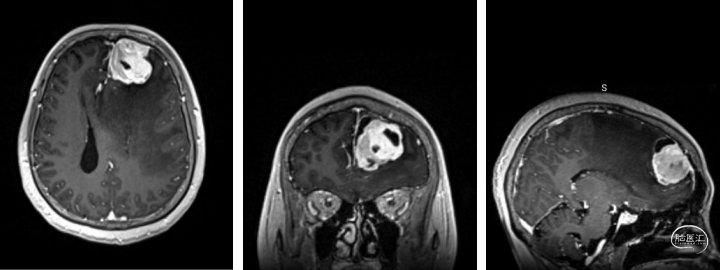

入院后增强头颅MRI影像学资料:

术前增强头颅MRI提示:左侧额叶占位,大小约3.8x3.6x3.9cm,增强扫描呈明显强化,其内见囊变区,伴瘤周水肿,中线结构右偏约1.8cm。考虑肿瘤性病变合并大脑镰下疝形成可能。